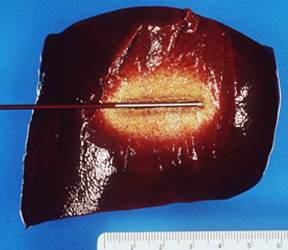

Scopul ablatiei cu radiofrecventa RFA este de a distruge in totalitate o tumora fara a afecta parenchimul hepatic adiacent prin inducerea de leziune termica la nivelul tesutului prin energie electromagnetica. Sistemele RFA ofera siguranta, eficienta, reproductibilitate si predictibilitate.